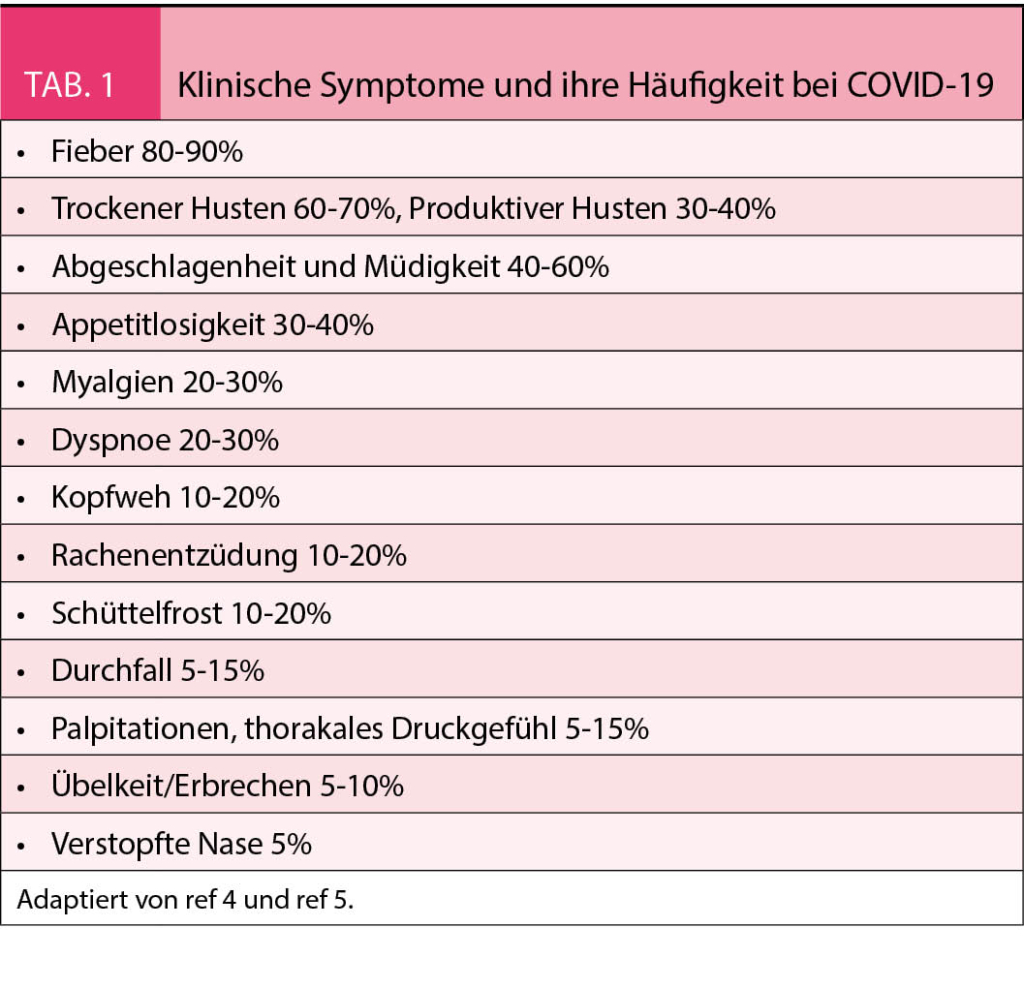

Es wird angenommen, dass die Übertragung vorwiegend über Tröpfchen des Atemsystems erfolgt, ähnlich wie bei der Influenza (4). Die Inkubationszeit variiert zwischen 2-14 Tagen. Angesteckte Individuen bleiben infektiös, d. h. können die Krankheit zwischen acht bis 37 Tage übertragen. Bei über 90% der Infizierten können aber 10 Tage nach Ausbruch der Symptome keine Viren mehr nachgewiesen werden. Wie allgemein bekannt, variiert die Klinik der Krankheit stark und die Schwere der Krankheit ist altersabhängig. Ein unbekannter, vielleicht beträchtlicher Teil der angesteckten Personen kann asymptomatisch bleiben. Interessanterweise finden sich aber auch bei asymptomatischen Patienten in 50% in einer CT-Untersuchung der Lunge die Zeichen der Infektion mit typischen retikulären Zeichen und Verschattungen. Die klinischen Symptome sind in der Tabelle 1 zusammengefasst. Die Krankheit beginnt meist mit Symptomen einer Infektion der oberen Luftwege und des Nasenrachenraums. Selten können Übelkeit und Durchfall die ersten Symptome sein (5). Eine Pneumonie mit Dyspnoe entwickelt sich meist über Tage. Damit einhergehend steigt das Fieber an, welches am Anfang der Infektion fehlen kann. Ausgeprägte Hustenattacken provoziert durch die Passage der Nahrung im Rachenraum kann die Nahrungsaufnahme bei einigen Patienten praktisch verunmöglichen. Hohes Fieber, Tachypnoe und Sättigungsabfall deutlich unter 90% sind die häufigsten Gründe für eine Hospitalisation. Von den wegen der Tachypnoe und Hypoxämie hospitalisierten Patienten müssen 75% intubiert und beatmet werden. Bei 50% der wegen des ARDS beatmeten Patienten kommt es im Verlauf zu einem Nierenversagen, welches eine Hämodialyse erfordert. Gegenwärtig laufen viele klinische Studien mit Medikamenten, die den Krankheitsverlauf in den verschiedenen Stadien günstig zu beeinflussen versuchen. Die wichtigsten sind in der Tabelle 2 aufgeführt. Die Beherrschung der Infektion ist aber schlussendlich nur durch einen potenten Impfstoff möglich.